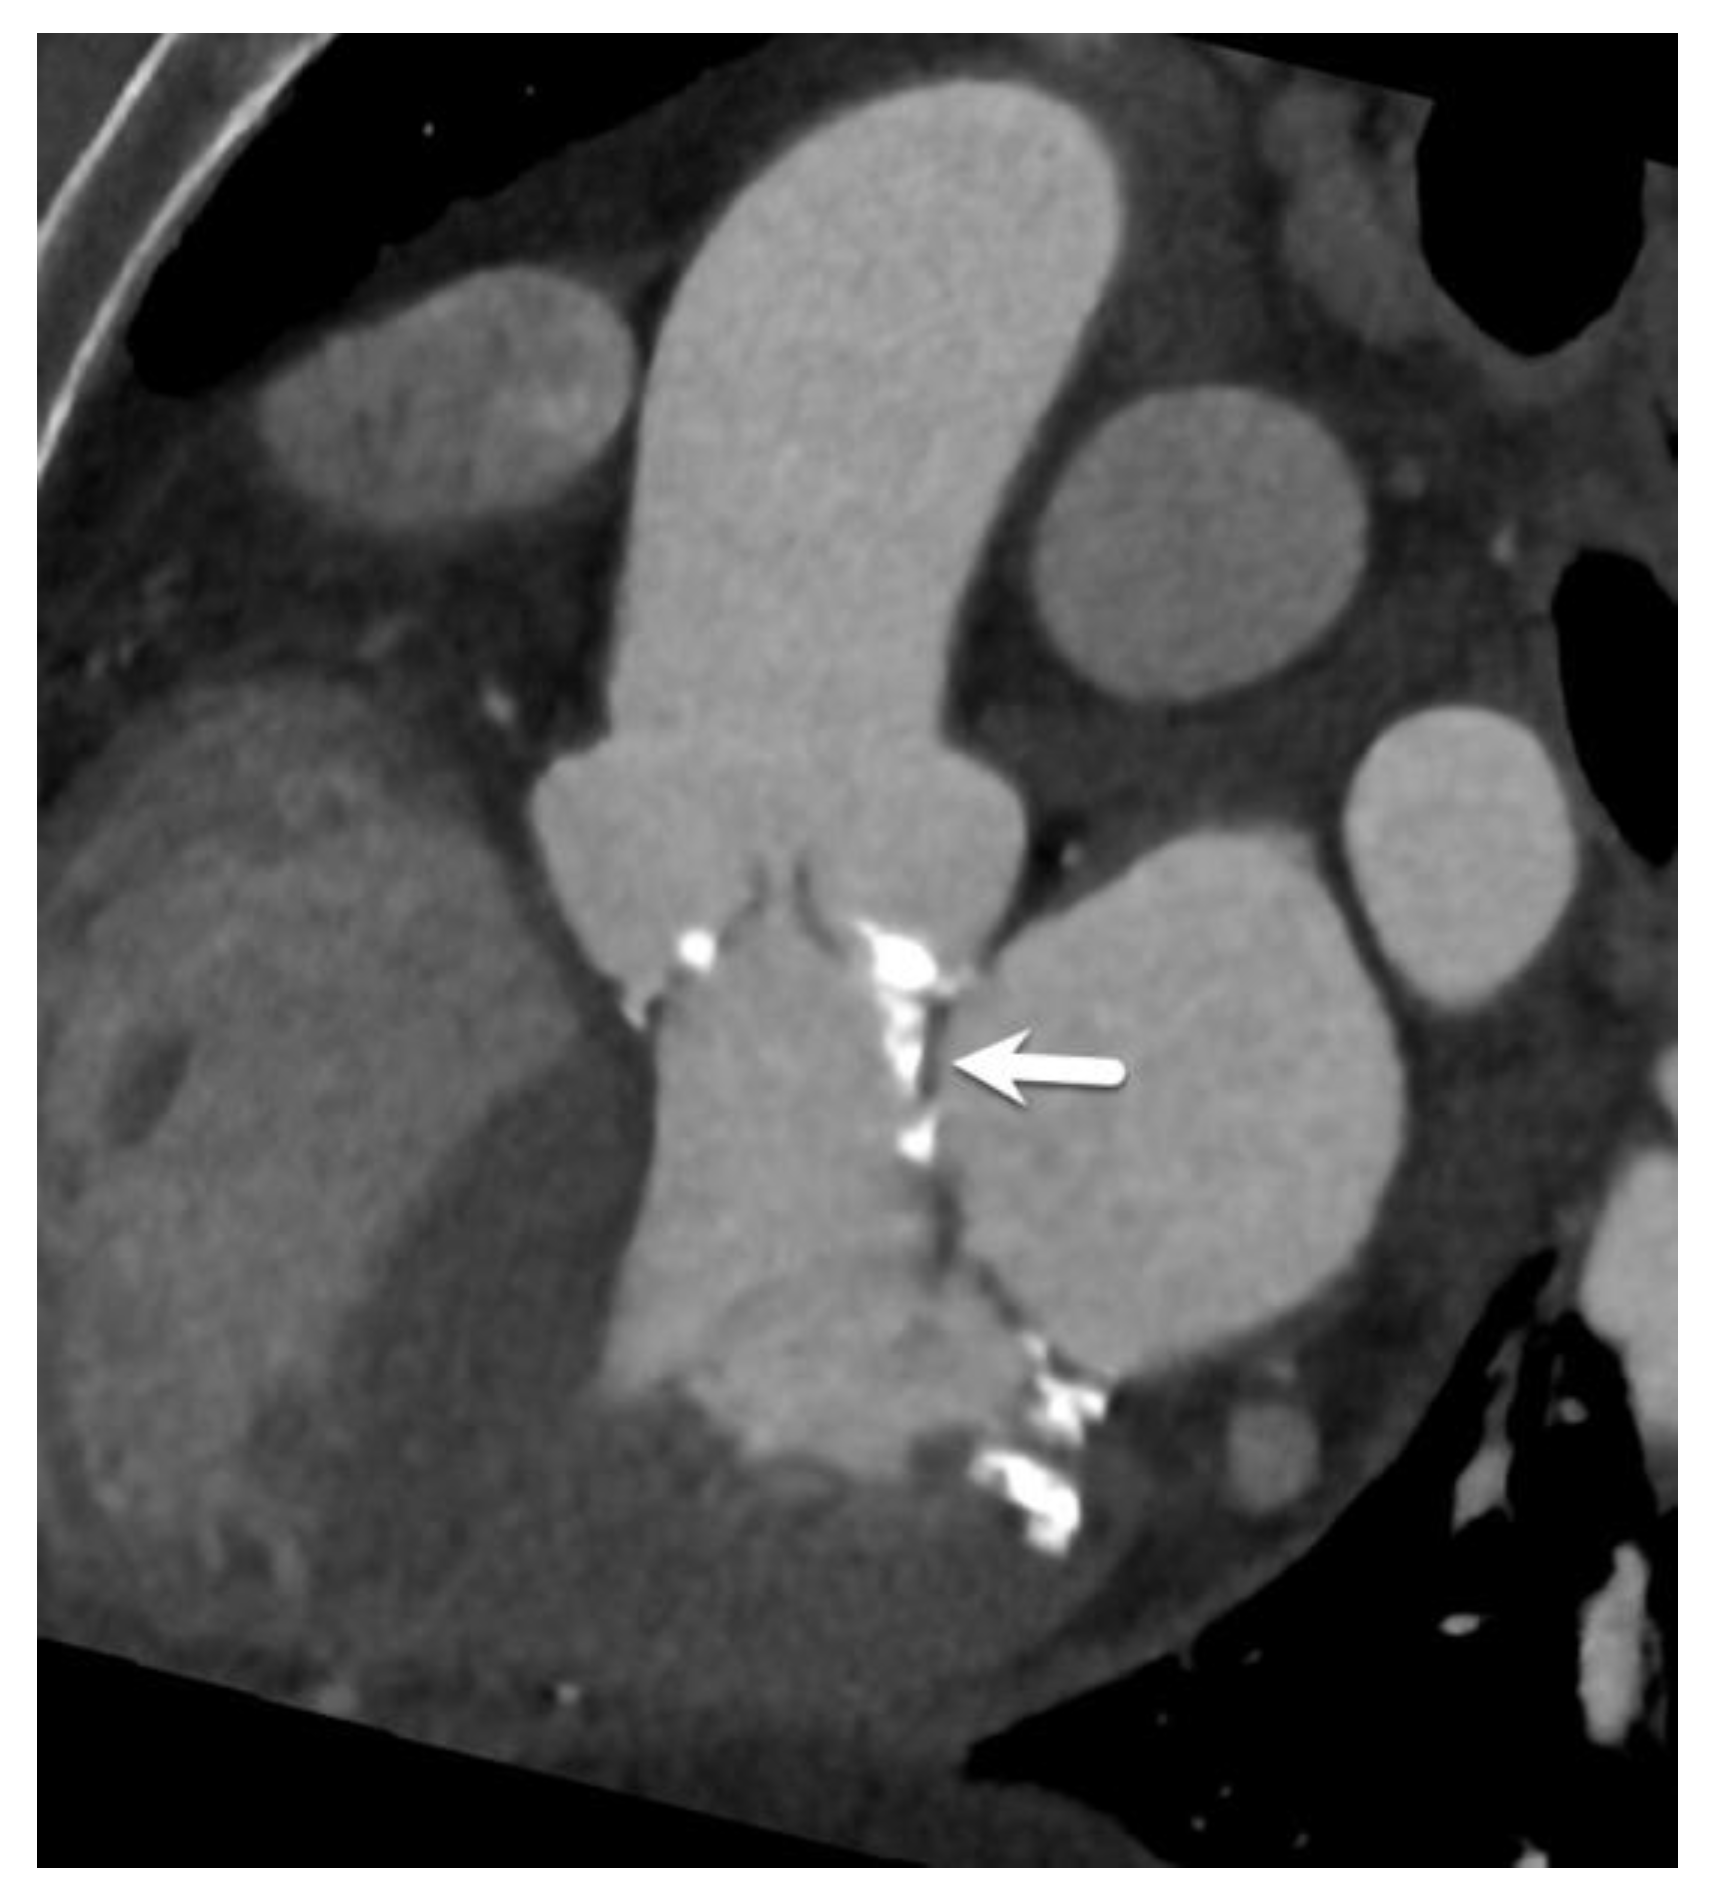

| Peripheral access vessel diameters | Minimal luminal diameters of the iliofemoral arteries | A minimal luminal diameter of 5–6 mm is generally required, depending on the delivery system. |

| Transfemoral | Most common and preferred approach. Access is typically through the femoral artery. | Least invasive. Preferred when feasible. | Requires an adequate iliofemoral vessel size and a lack of severe tortuosity/calcification. |

| Transapical | Through the left ventricular apex via small chest incision. | Option when transfemoral route not possible. Direct access to the aortic valve. | Only applicable to balloon-expandable valves. More invasive. Requires a normal LV apex. A steeper angle may complicate procedure. |

| Transaortic | Direct access to the ascending aorta via mini-sternotomy. | Option when transfemoral route not possible. | More invasive. The amount/location of ascending aorta wall calcification is important, typically at about 6 cm above the annular plane. |

| Subclavian/axillary | Through the subclavian or axillary artery. | Alternative when transfemoral route not possible. | Left side preferred due to angulation. |

| Transcarotid | Through the common carotid artery. | Alternative when other routes not possible. | Less commonly used. |

| Transcaval | Through the inferior vena cava and across the abdominal aorta. | Option in severe peripheral vascular disease. | Complex technique. Calcification-free window in aorta needed. Seldom used. |